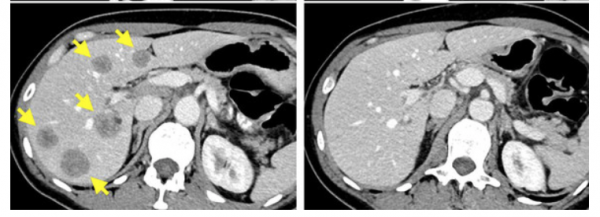

Al aislar y reactivar las células T de esta paciente cuyo cáncer estaba progresando, se eliminaron las lesiones metastásicas y la mujer pudo estar dos años sin tratamiento. La detención del crecimiento y la diseminación del cáncer atacando proteínas o genes específicos será la nueva forma de tener éxito en pacientes con cáncer de mama que hayan tenido tratamientos ineficaces antes.